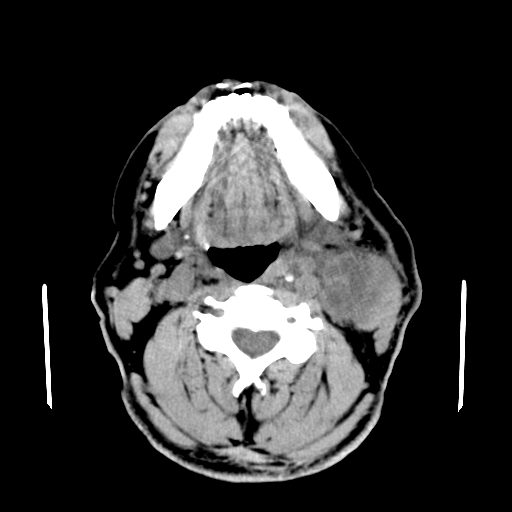

以下是引用卜一在2007-8-6 21:23:00的发言:[br]定位:左侧胸锁乳突肌内侧 颌下腺下后方。特征:弥漫性生长 软组织密度肿块,界限不清,内隐约见低密度坏死。考虑:神经源性肿瘤或血管源性肿瘤。

以下是引用wangzhanshuang在2007-8-6 21:08:00的发言:[br]腮腺混合瘤